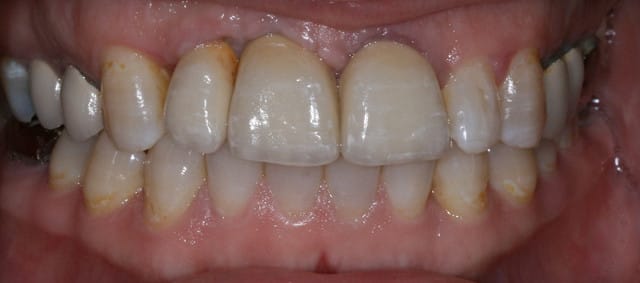

Bon finalement je vous poste le cas terminé.

La prochaine fois je ferrai une greffe d'apposition comme j'avais pu le préssentir... Ca me permettra de garder les papilles.

A la prochaine séance je gomme la coloration mésiale de 12, c'est promis ;+)

Un cas pas évident... l'important est que la patiente soit contente à la fin.

08/10/2011 à 15h07

Mon DuDule quel dommage que tu n'ai pas un ditramax car ta ligne interincisive n'est pas parallèle au plan médian et la ligne des bords libres pas parallèle à la ligne blanche masquant les yeux!

Sinon chirurgicalement c'est sympa compte tenu du terrain initial